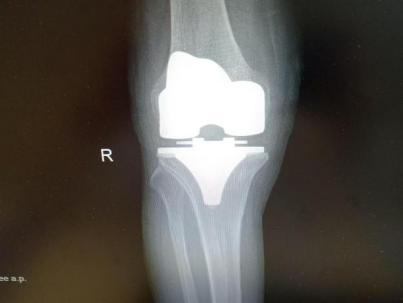

多年来,贵州航天医院各科室紧跟医学前沿,不断强技术、补短板,大力开展新技术、新项目,完成了许多高精尖、高难度、本地区“首例”的技术,填补了医院医疗技术空白,满足了群众日益增长的医疗需求。 贵州航天医院骨科率先在遵义地区开展骨搬移技术,截至目前,已治愈慢性骨髓炎、感染性骨不连、骨缺损、脉管炎、糖尿病足患者200余例,糖尿病足治疗保肢率达到98%。 本期,我们将为大家带来骨科特色技术——骨搬移技术(Ilizarov)。 案例分享 一名59岁的患者,身患糖尿病12年,在来我院3个月前出现了右脚溃烂的症状,来院就诊时,患者的右脚十分红肿,右脚脚趾坏死,伤口处不断流出黑红色脓液,情况十分严重。在接诊到患者时,骨科专家团队高度重视,立刻为患者完善了CT血管造影(CTA)等相关检查,诊断为:2型糖尿病,糖尿病周围血管病变,右糖尿病足。 术 前 考虑到患者情况比较严重,为最大限度保证患者肢体完整,科室专家团队进行了严格的讨论评估,为患者制定了骨搬移技术治疗方案,在征得患者及其家属的同意后,成功通过搬移骨块为患者进行治疗,促进患者病变肢体血管再生。 胫骨横向骨搬移外架固定 清除感染病灶 术后调节外架,通过搬移骨块 促进患肢血管再生 患者在术后三周前来换药,观察到感染得到进一步控制;术后六周复查,患者病变处已愈合,进行CT血管造影(CTA)后可明显观察到足部血管再生。 术后3周 术后6周愈合 CT血管造影见足部血管再生 糖尿病患者全身与局部的问题互为影响,形成恶性循环,糖尿病足溃疡创面迁延不愈,常见干性坏疽、湿性坏疽、趾坏死、深且大的溃疡以及骨髓炎等症状,还可导致脓毒血症,以往为保全生命,患者被迫选择一次或多次截肢。骨搬移技术的发展进步,能在血糖有效控制、局部有效清创下,有效促进患肢微血管再生,改善患肢血供,达到糖尿病足更快治疗康复的目的,并能根据病变情况最大限度的保障患者肢体完整。 什么是骨搬移技术 骨搬移技术是通过使用专用的骨外固定器固定骨段,每天缓慢牵拉,在牵拉搬移过程中,骨段尾部形成新骨及新的软组织,从而修复骨骼缺损及软组织缺损。是治疗大段骨缺损、骨不连、骨感染、肢体畸形的金标准方法,也用于治疗脉管炎、糖尿病足等肢体缺血性疾病。 骨感染缺损 切除感染段 搬移骨段 新骨形成 骨感染根治愈合 骨搬移技术原理 生物组织在持续、稳定、缓慢牵拉下,能刺激细胞分裂、组织再生,骨外固定技术运用该原理,通过持续缓慢调节外固定器形成牵拉张力,促进牵引成骨与相邻组织再生,如神经、血管、肌肉、皮肤等再生,达到治疗大段骨缺损、肢体缺血如糖尿病足等疾病的目的。 骨搬移技术优势 (一)除治疗骨缺损、骨不连外,有更广的适用范围,利用组织再生、血管再生等特性,能大量运用于肢体畸形的矫形、糖尿病足等的治疗。 (二)治疗效果确切,重建肢体外型和功能,极大降低截肢率和残疾率。 (三)明显提高了患者生活质量,极大减轻其家庭及社会负担。 肢体畸形的矫形 慢性骨髓炎 骨段切除 术后1年 濒临截肢的脉管炎术后6周 难愈创面术后3周 贵州航天医院骨科 专家团队 赵学平 骨科主任 主任医师 临床擅长:从事骨科临床工作30余年,对骨科常见疾病的诊治具有丰富的临床经验。 世界中医药联合会脊柱康复专业委员会常务理事,中华中医药学会整脊分会常务委员,中国中西医结合学会骨伤科分会肢体矫形功能重建与康复专家委员会常务委员,中国研究性医院学会骨科创新与转换专业委员会关节外科学组保髋工作委员会常委,中国康复技术转化及发展促进会骨外科与康复技术转化专业委员会常务委员,泛珠三角区域运动医学联盟(PPRD-SMA)理事会常务理事,中国研究型医院学会运动医学专业委员会委员,贵州省中医药学会整脊分会副主任委员,贵州省中西医结合学会银质针专业委员会副主任委员,贵州省康复医学会骨与关节专业委员会常务委员,贵州省人民医院骨科专科联盟常务理事,贵州省康复医学会骨内科专业委员会常务委员,中华医学会贵州省骨科学会委员,贵州省康复医学会脊柱脊髓专业委员会常务委员,贵州省运动医学分会委员,贵州省康复医学会骨与软组织肿瘤专业委员会委员,遵义市医学会创伤分会副主任委员,贵州省康复医学会骨内科专业委员会遵义地区分会常务委员,遵义市医疗事故鉴定、伤残鉴定、工伤鉴定、司法鉴定专家。 长期从事骨科临床研究及教学工作,在国家级、省部级杂志发表论文20余篇,SCI论文2篇,参与主编骨科专著2部,主持省部级科研项目2项,参与指导省部级、市级科研项目6项。 陈明勇 骨科副主任 副主任医师 临床擅长:从事创伤骨科工作约20年,对骨缺损、骨不连、骨肿瘤、肢体畸形等的肢体矫形重建及功能重建,慢性化脓性骨髓炎的根治治疗、糖尿病足的保肢治疗、快速康复理念(ERAS)下的老年骨折的诊治,四肢复杂骨折的诊治,四肢骨折等微创手术治疗具有丰富的临床经验。 2004年毕业于遵义医学院临床专业,曾在中国人民解放军总医院、广西医科大学第一附属医院、上海第六人民医院骨科进修。中国中西医结合学会骨伤科专业委员会横向骨搬移治疗糖尿病足及微血管网再生学组首届委员,遵义市医学会创伤分会常务委员。 瞿 辉 骨科 副主任医师 临床擅长:对骨科的常见病、关节外科、脊柱外科及运动医学疾病的诊治具有丰富的临床经验,熟练掌握骨科手术操作技术。 毕业于遵义医学院临床医学系,2005年前往广州中山大学第一附院骨显微医学部进修学习,2011年前往成都华西医院进修学习,并多次在省内外学习骨科相关知识,是中华医学会骨科分会会员。 赵兴东 骨科 主任医师 临床擅长:擅长骨科的常见病及各种创伤、四肢骨折创伤修复、骨感染、手足疾病的诊治和手足体表畸形的矫形整复,熟练掌握骨科四肢骨病及创伤的手术操作技术,尤其在四肢关节复杂性损伤、手足外伤、组织缺损创面、难治创面的皮瓣修复方面及平足、高弓足矫形方面及四肢慢性疼痛诊治、康复方面具有丰富的临床经验。 硕士研究生,毕业于遵义医学院临床外科系,2015年前往山东省立医院手足外科进修学习;遵义市医学分会创伤分会第一、二届委员,遵义市手外科医学会第二委届员会常务委员;在省级及省级以上期刊发表文章9篇,参编著作2部,参与主持并完成市级课题1项,参与市级课题2项、省级课题1项。 张俊凯 骨科 副主任医师 临床擅长:从事骨科临床工作28年,对创伤骨折、骨感染、骨缺损、骨不连等外科诊治,四肢骨折的微创手术治疗,四肢复杂骨折(如关节内粉碎性骨折、多发骨折等)的损伤控制及手术治疗等具有丰富的临床经验。 1995年毕业于遵义医学院临床专业,2009年前往复旦大学附属医院骨科进修1年。 卢懿明 骨科 副主任医师 临床擅长:从事骨科工作18年,对创伤骨折、四肢骨折的微创手术治疗、四肢复杂骨折(如关节内粉碎性骨折、多发骨折等)的损伤控制及手术治疗,尤其是髋部骨折的PFNA等微创技术,踝关节骨折、膝关节周围骨折的Mipo微创技术等具有丰富的临床经验,开展了4项新技术,发明6项新型专利技术。 2005年毕业于遵义医学院临床专业,2017年,前往南方医科大学第三附属医院骨科进修半年,回院后运用Mipo技术对骨干骨折及干骺端骨折的治疗技术,同时积极开展骨盆骨折、髋臼骨折腹直肌外侧切口的应用;发表了多篇专业论文,经常参与省内外学术交流会授课,获得医院荣誉称号多个。 邬夏荣 骨科 副主任医师 临床擅长:从事骨科工作16年,对四肢复杂骨折、骨肿瘤的诊治,尤其是足踝创伤、慢性踝关节损伤、平足症等诊疗具有丰富的临床经验。 2006年毕业于遵义医科大学临床医学专业,曾在陆军军医大学西南医院进修学习,发表多篇骨科学术论文。 余德怀 骨科 副主任医师 临床擅长:从事骨科工作10余年,对运动医学、骨关节、脊柱外科常见病、多发病的诊治具有丰富的临床经验。 硕士研究生,2011年毕业于遵义医学院临床医学专业,曾前往遵义医科大学附属医院运动医学专业进修学习;是贵州省医学会运动医学分会青年委员,西部关节镜联盟委员;发表多篇骨科学术论文。 冯 乾 骨科 副主任医师 临床擅长:从事骨科工作近20年,熟练掌握骨科多发病及常见病的诊治,尤其对脊柱退变性疾病的诊断及治疗具有丰富的临床经验,主要研究脊柱微创相关治疗方式,能熟练开展椎间孔镜及VBE。 曾前往北京大学第三医院进修学习疼痛及椎间孔镜、首都医科大学友谊医院专业进修脊柱内镜;是贵州省康复医学会第三届脊柱脊髓专业委员会委员;发明专利3项、发表脊柱外科专业论文多篇。 张艳金 骨科 副主任医师 临床擅长:从事骨外科工作16年,对复合伤、多发伤的救治、四肢骨干骨折、关节周围骨折、骨肿瘤、骨髓炎等诊治具有丰富的临床经验。 中共党员,硕士研究生,2006年本科毕业于山西医科大学第二临床医学院,2011年研究生毕业于北京军区总医院;在“老年COPD患者合并髋部骨折的诊治”国际合作课题组研究两年,在老年髋部骨折的诊治方面具有丰富的经验,并发表论文6篇;承担遵义市级课题1项;承担遵义医科大学的临床教学工作,获得遵义医科大学优秀带教老师荣誉。编撰有《骨科疾病诊疗精粹》一书,开展2项新技术,编撰地方规范《务川自治县创伤骨科常见疾病诊疗规范》一书。 赵小锋 骨科 副主任医师 临床擅长:从事骨科临床工作11年,对骨科常见病、多发病诊疗有较为丰富的临床经验,擅长脊柱相关疾病诊断及治疗,尤其是颈、腰、腿疼痛疾病诊断及治疗,擅长胸腰椎骨折微创经皮穿刺内固定术、经皮穿刺椎体成形术、经皮穿刺脊柱内镜下腰椎间盘摘除术、单纯开创腰椎间盘摘除术、腰椎滑脱复位椎间植骨椎融合内固定术、腰椎管狭窄减压融合内固定术及人工髋、膝关节置换术等。 2012年毕业于遵义医学院外科学专业硕士研究生,2019年参加“遵义市115医学人才精英计划”于上海交通大学第一附属医院培训学习,2023年于北京大学第三人民医院脊柱外科进修学习,曾获得遵义市优秀医师荣誉称号。 遵义市手外科第一届委员,遵义市医学会创伤分会第一届委员,遵义市医学会创伤分会第二届委员,贵州省康复医学会第三届脊柱脊髓专业会委员,遵义市医学会烧伤与整形外科学分会委员,发表论文5篇,其中国家级核心期刊1篇,SCI论文1篇,主持市级课题1项并结题,参与市级课题2项。 贵州航天医院骨科简介 基本情况 贵州航天医院(原3417医院)骨科组建于1968年,前身是以创伤和断肢(断指)再植闻名于世的上海市第六人民医院骨科,中国断肢(断指)再植的奠基者、中科院院士陈仲伟等著名专家、学者多次莅临科室指导医疗、教,是贵州省最早拥有专业骨科技术科室之一,在70年代开展了贵州省首例断肢(断指)再植手术。组建50余年来,诊治患者已逾百万,挽救了无数的伤病员,成为了保障遵义地区人民群众健康的重要支撑。 经过几代人的不懈努力,今天的骨科,已由创伤骨科发展至骨病、骨肿瘤、骨结核等领域,现有脊柱外科、关节外科、四肢创伤、手足外科四个亚专科,成为了集医疗、教学、科研于一体的综合学科,是贵州省临床重点专科、遵义市临床重点专科、遵义市骨科临床医学中心、遵义市基层骨科专科联盟理事长单位。 科室目前开放床位110张,共有医护人员50余人,副高级以上专家18人,硕士研究生15人。拥有一流骨科医疗设备多台,每年不定期选派优秀技术骨干到全国各大知名医学院校进修、学习、参观、交流,并邀请国内、国外知名专家教授来院进行交流、指导,通过不断引进国内外先进的诊疗技术,科室医疗技术水平稳步提升,为广大人民群众提供了优质的医疗服务。 专科特色 骨一科 (一)骨缺损、骨不连的肢体与功能重建 胫骨横向骨搬移技术治疗糖尿病足: (二)慢性骨髓炎的根治治疗 (三)肢体缺血性疾病如糖尿病足、脉管炎的保肢治疗 (四)皮瓣修复 (五)复杂创伤的治疗 (六)老年髋部骨折及小儿骨折快速手术 老年髋部骨折: 骨二科 (一)胸腰椎骨折微创经皮椎弓根螺钉固定术 (二)老年性骨质疏松性患者腰椎滑脱脊柱内固定术(骨水泥螺钉) (三)V形双通道脊柱内镜技术(VBE)腰椎融合术治疗腰椎退行性疾病 (四)老年性骨质疏松性骨折(PVP/PKP)术 (五)人工髋关节置换术 (六)双侧股骨头坏死人工全髋关节置换 (七)右侧全髋置换术后假体周围骨折翻修 (八)人工膝关节置换术 (九)人工膝关节假体松动翻修 (十)关节镜技术 传统手术切口 关节镜技术切口 诊疗范围 骨一科 1.四肢创伤、矫形。 2.手、足踝外科。 骨二科